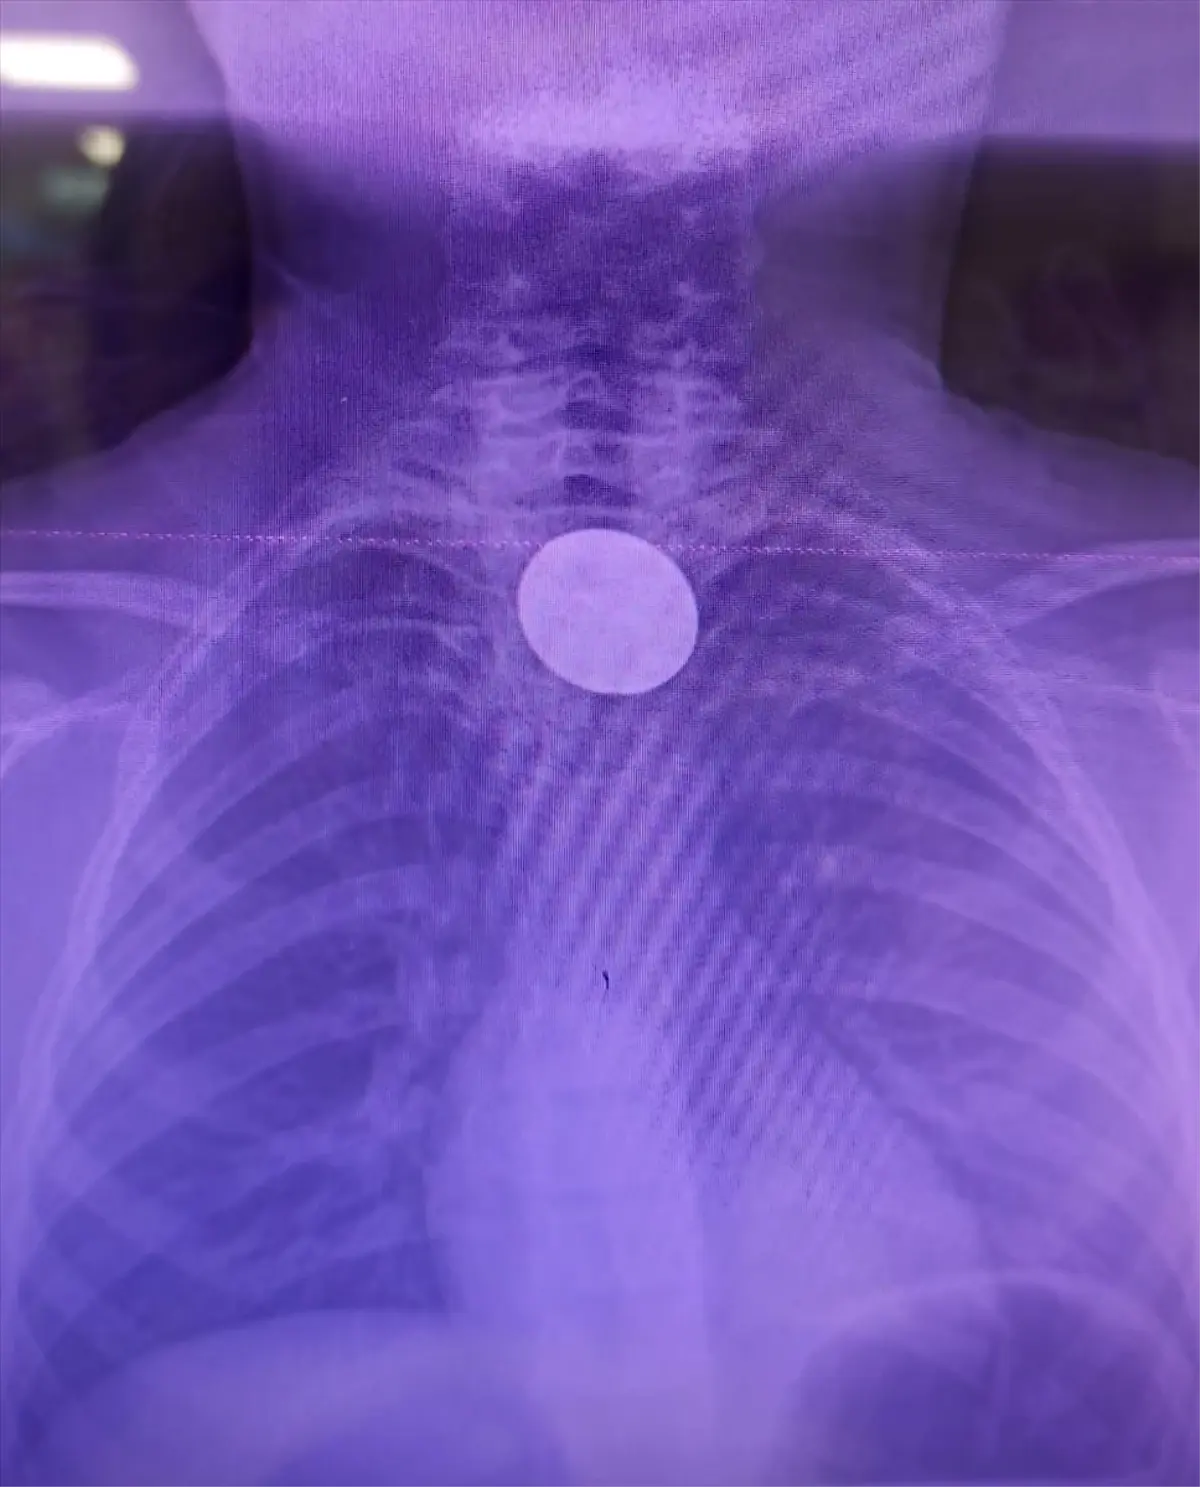

Siirt’te 8 Yaşındaki Çocuğun Boğazına Takılan Madeni Para Acil Müdahale ile Çıkarıldı

Siirt’te bir çocuğun boğazına kaçan madeni para, hastane ekiplerinin hızlı müdahalesiyle çıkarıldı;...